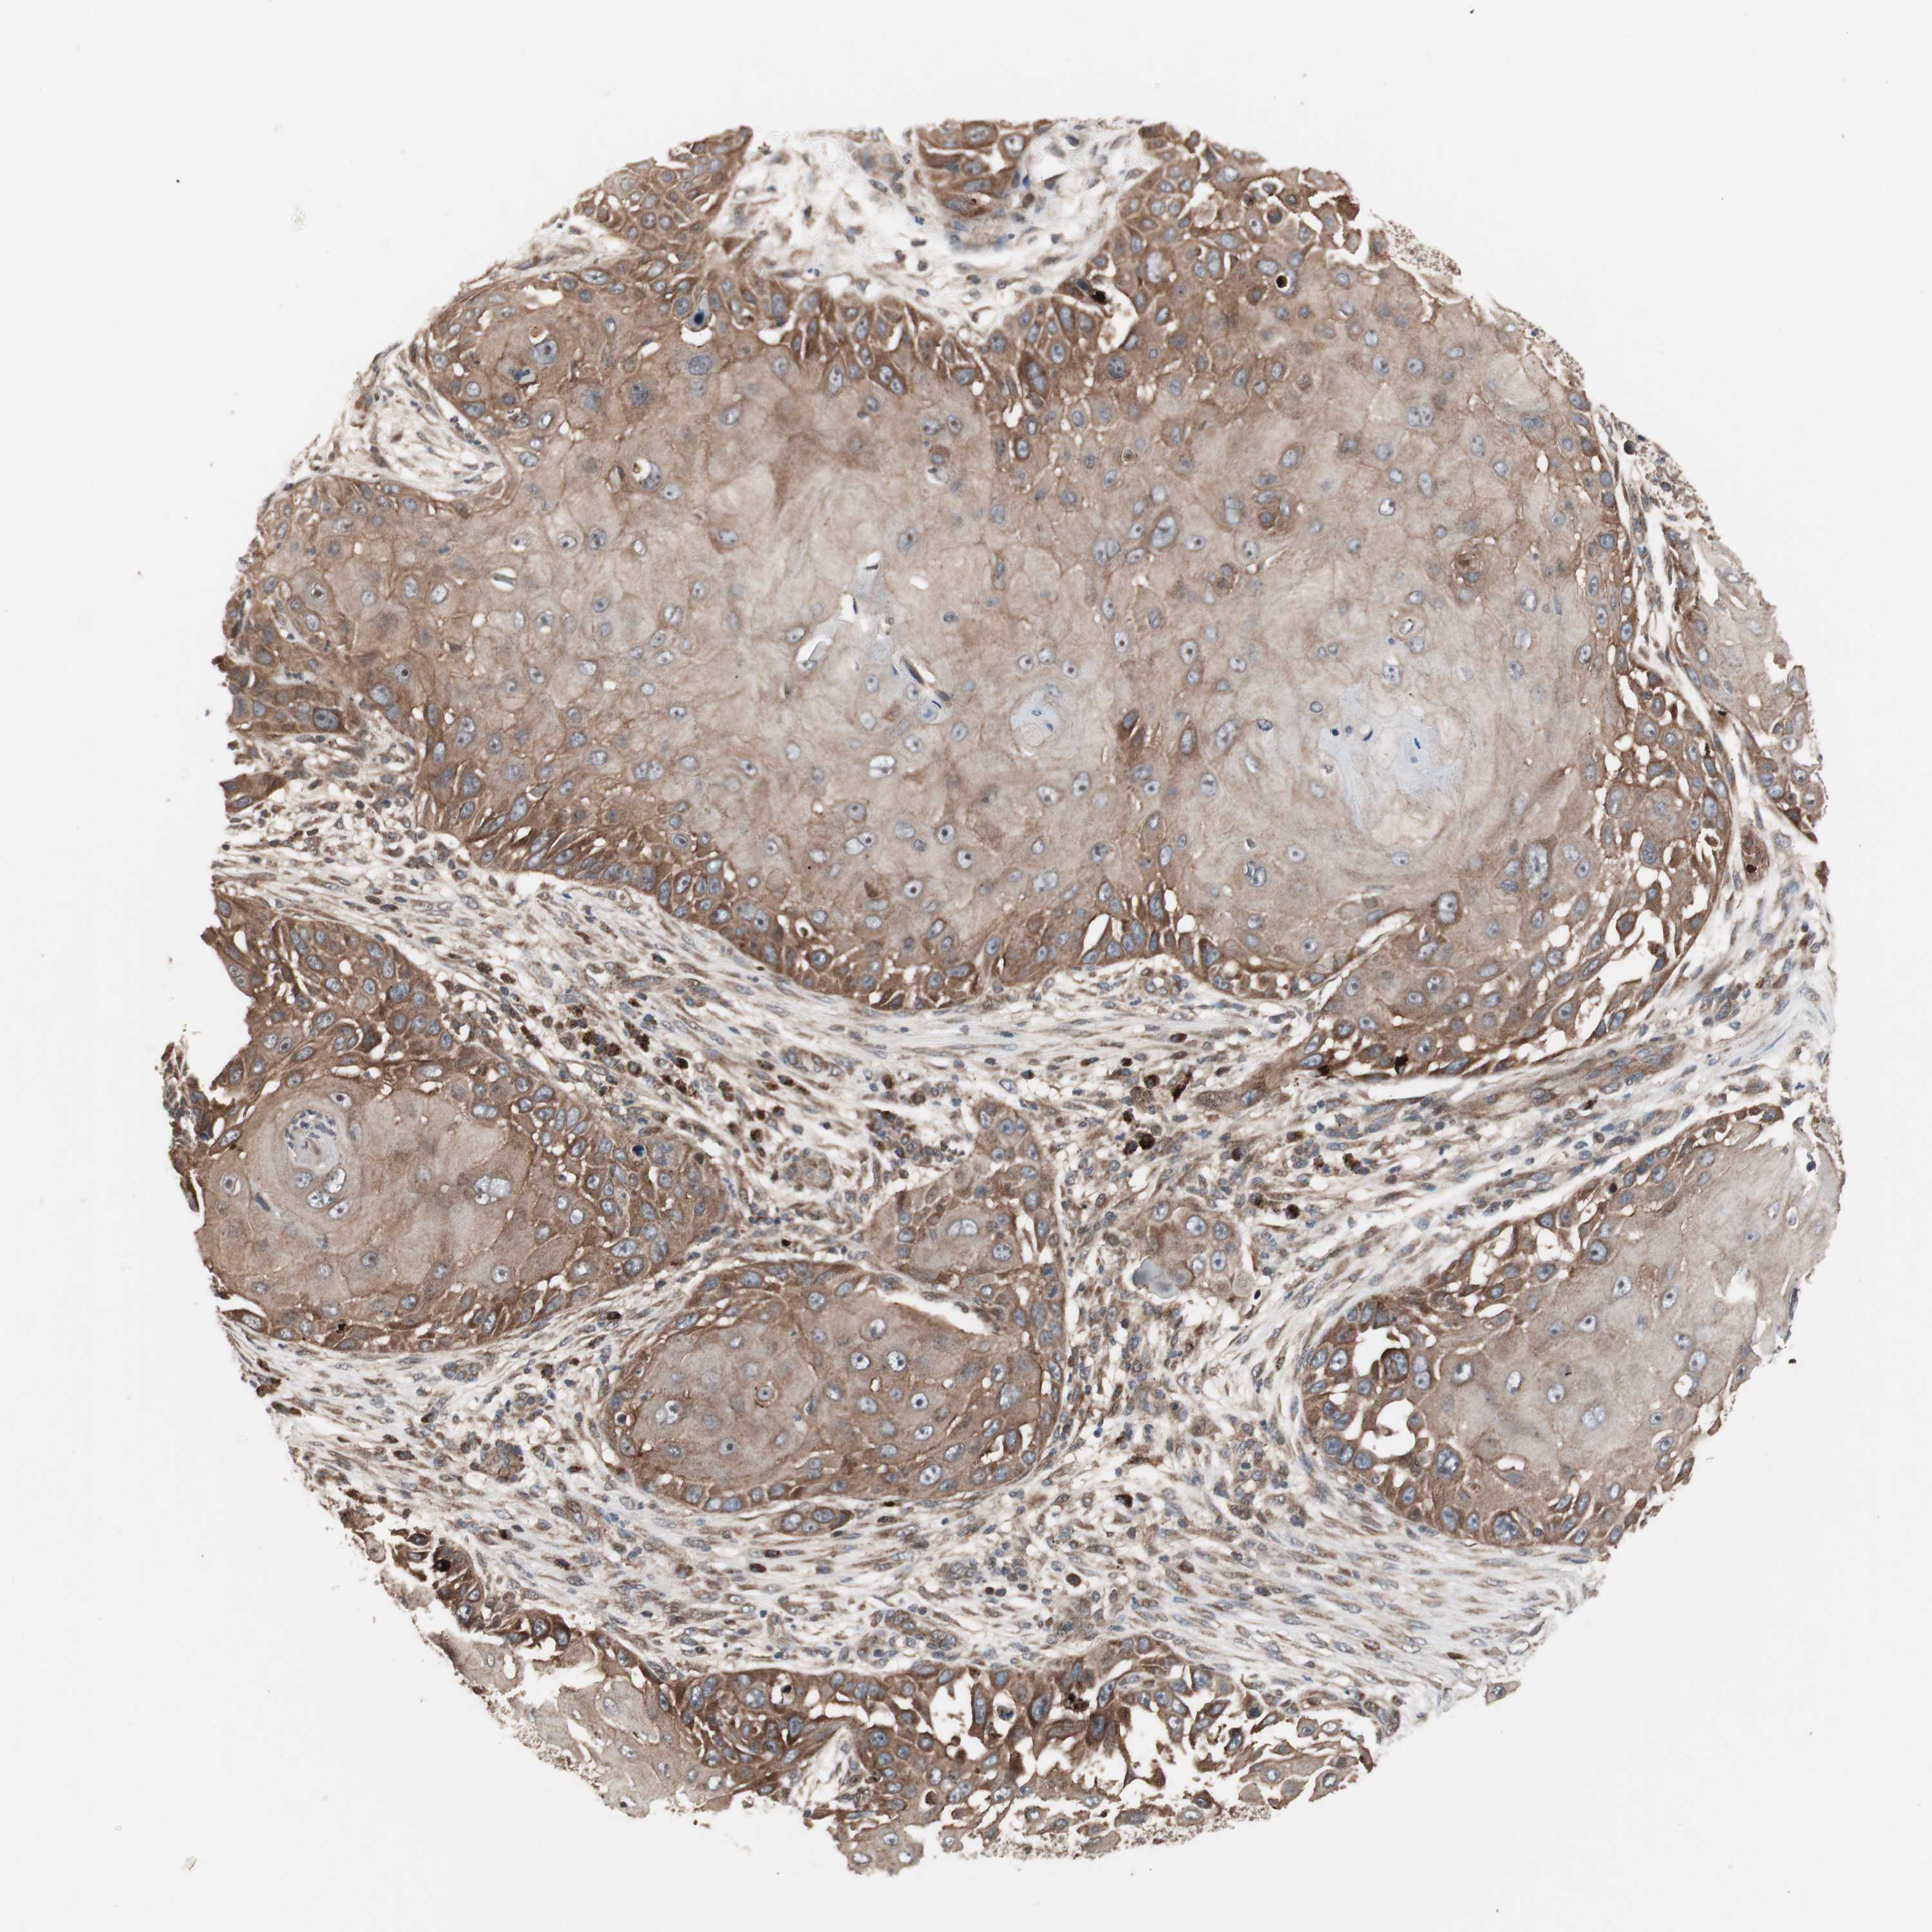

SKIN CANCER - Protein expressioni

A mouse-over function shows sample information and annotation data. Click on an image to view it in a full screen mode. Samples can be filtered based on level of antibody staining by selecting one or several of the following categories: high, medium, low and not detected. The assay and annotation is described here.

Antibody stainingi

Antibody staining in the annotated cell types in the current human tissue is reported as not detected, low, medium, or high, based on conventional immunohistochemistry profiling in selected tissues. This score is based on the combination of the staining intensity and fraction of stained cells.

Each image is clickable and will lead to virtual microscopy that enables deeper exploration of all samples and also displays staining intensity scores, fraction scores and subcellular localization as well as patient and tissue information for each sample.

Antibody HPA003097

Staining

High

Medium

Low

Not detected

Intensity

Strong

Moderate

Weak

Negative

Quantity

>75%

75%-25%

<25%

None

Location

Nuclear

Cytoplasmic/membranous

Cytoplasmic/membranous,nuclear

Squamous cell carcinoma, NOS